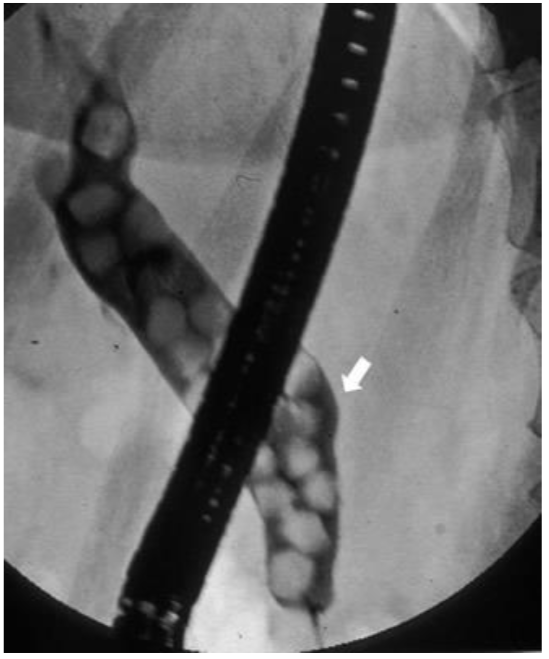

A 47-year-old woman complaining of abdominal pain was found to have jaundice on examination. An ERCP was done and showed a dilated bile duct that is completely blocked by stones. What values do you expect on further investigation?